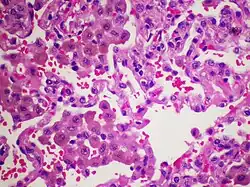

El diagnóstico se sospecha por los síntomas, los antecedentes de tabaquismo intenso y las pruebas de imagen. Sin embargo para llegar al diagnóstico de certeza es preciso realizar una biopsia pulmonar. Las principales alteraciones anatomo-patológicas se observan en las estructuras alveolo-intersticiales, es característica la presencia de abundantes macrófagos en los alveolos pulmonares y la existenicia de un infiltrado inflamatorio septal constituido por linfocitos, eosinófilos e histiocitos.[6]